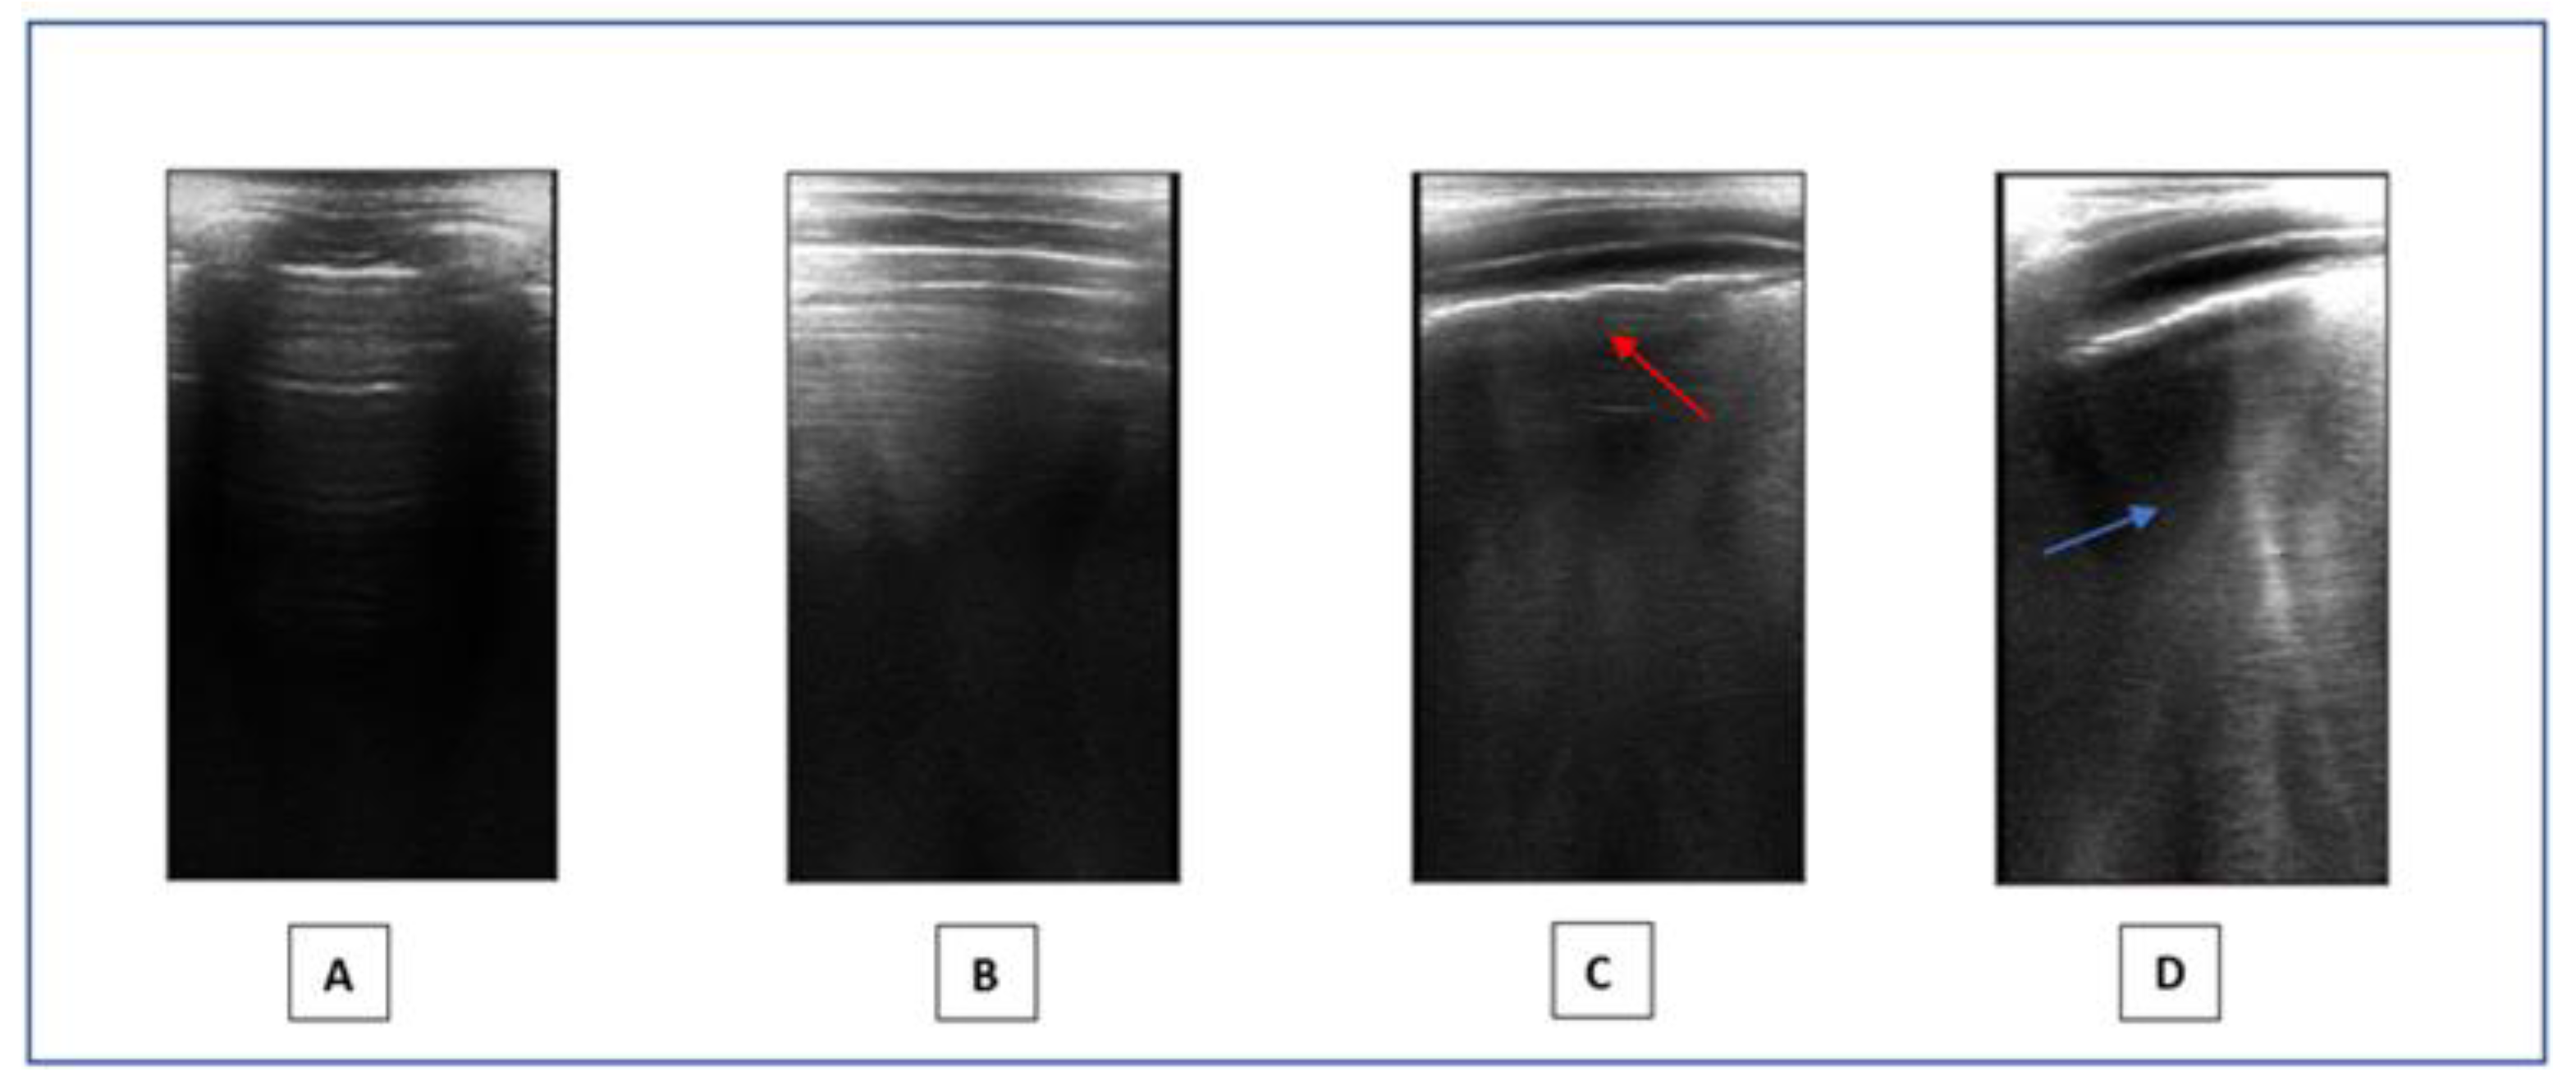

- Lung ultrasound: LUS is a non-invasive method that provides a real-time image of lung structures, enabling doctors to identify early alterations in lung function. The radiation-free approach and portability of ultrasound make it an attractive choice in children, helping to limit exposure to X-rays. LUS has gradually expanded its use to encompass various pediatric applications, including all types of pneumonia, pulmonary embolism, and typical chest and lung diseases in childhood [53]. Lung semiotics consists of artifacts originating from the air/tissue interface and authentic images, like effusions and consolidations [54]. Non-pathological ultrasound images exhibit A-lines and a consistently thin pleural line. Conversely, abnormal images are identified by the observation of three or more B-lines between two ribs in a single scan with the disappearance of A-lines, indicating subpleural interstitial edema, up to a ‘white lung’ picture, consolidations, an irregular or thickened pleural line, and pleural effusion (Figure 1). LUS is a very effective and sensible method for assessing the presence of small pleural effusion. Furthermore, in the diagnosis of childhood pneumonia, lung ultrasound (LUS) is considered as an imaging alternative to computed tomography (CT) scans, as LUS findings demonstrate a significant correlation with those observed in chest CT scans [55]. Nonspecific abnormalities, such as the presence of multiple bilateral B-lines, indicating a reduction in air content, thickening of the pleural line with associated abnormalities, and peripheral consolidation, may be observed on the LUS scans of children with COVID-19 pneumonia [56]. Since the early stages of the pandemic, LUS has demonstrated to be a helpful tool to assess lung conditions, monitor any changes over time, and guide therapeutic decisions in both adults and children [57,58,59,60,61]. The LUS in this study was conducted using a linear probe. We adhered to a standardized approach regarding acquisition protocol, as previously outlined by Volpicelli et al. [62]. We examined a total of 12 thoracic areas: 2 anterior, 2 lateral, and 2 posterior areas on each side. Based on the severity of the findings, a numerical score between 0 and 3 was assigned: 0 = normal; 1 = irregular pleural line with less than three B-lines between two ribs in a single scan; 2 = irregularities of the pleural line with more than three B-lines between two ribs in a single scan; 3 = areas of consolidations or ‘white lung’. Each LUS was performed by the same doctor, Dr. A.K., who is a pediatrician and a certified expert operator in pediatric lung ultrasound.